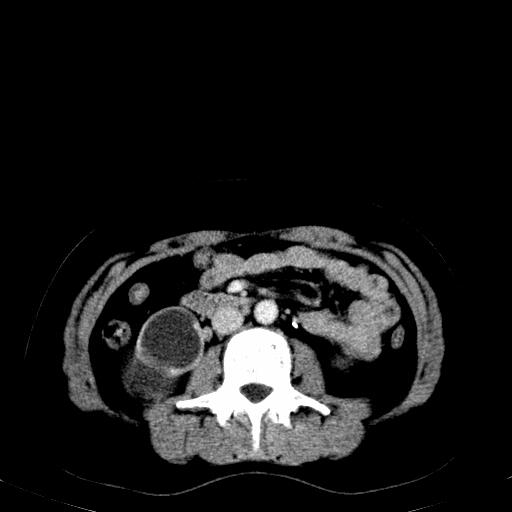

患者体检发现右肾体积增大,怀疑右肾积水

右肾多发囊肿,左肾、左输尿管结石

右肾重度积水,以肾盏积水明显,有分隔,上段输尿管轻度扩张,管壁增厚,考虑肾结核可能,请结合尿检查,胸部拍片排除肺结核。

右肾重度积水,建议ct向下扫描或逆行造影,左肾及左输尿管结石 .

1)不排除右肾结核可能。2)左肾及左输尿管上段结石?

结合强化图片看ivp意义不大,建议作逆行造影看一下;

左肾不是结石,是造影后改变.右肾积水,功能仅存.